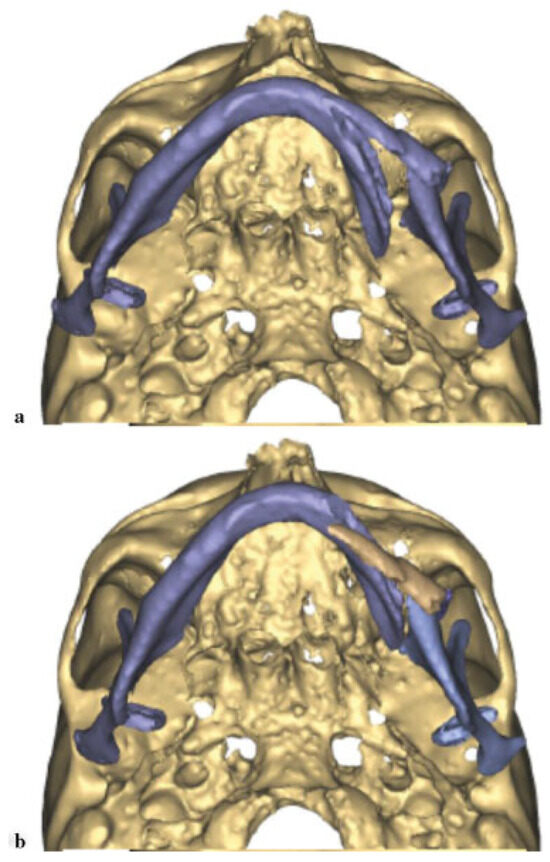

Prior to surgery, VSP was implemented to plan the procedure (Materialize, Plymouth, MI). A CBCT was obtained. Similar to the previous case, the midline of the major segment was aligned with the midline of the maxilla (Figure 7a,b). The displaced smaller segment was placed in the glenoid fossa and the inferior borders were aligned. A mirror image of the unaffected right side of the mandible was then superimposed. The area of lytic bone was outlined and a model was fabricated. A 2.5-mm locking reconstruction plate was prebent according to the 3D model using the mirror image model with enough length to span the area that would be reconstructed (Figure 8).

Figure 7. (a) Displacement of the jaw prior to manipulation. (b) Alignment of the midline of the mandible with the maxilla revealing the large defect on the jaw lateral border.